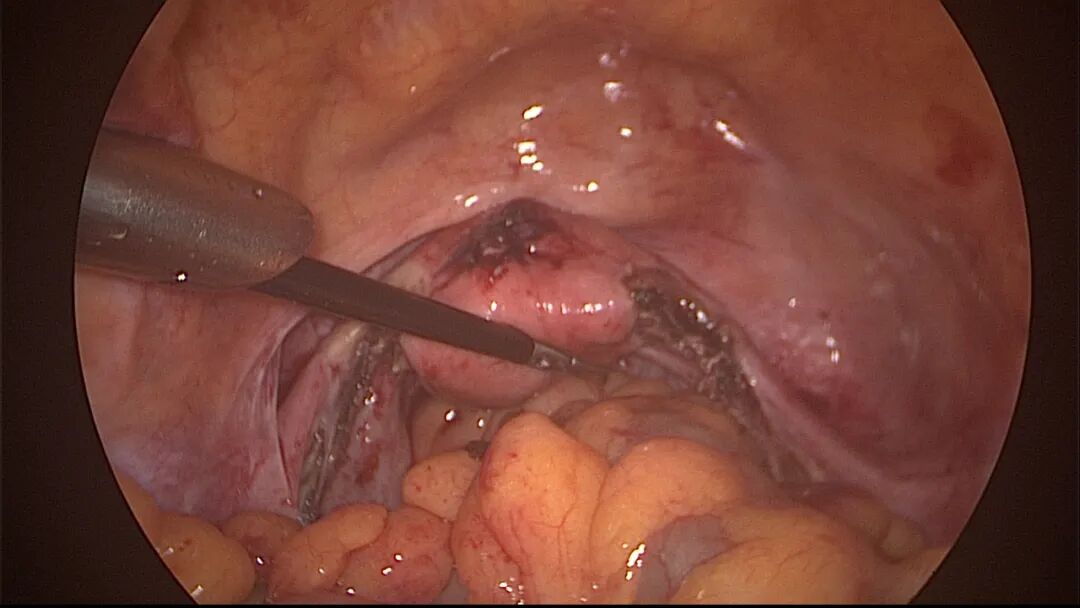

外院取环失败,子宫穿孔,盆腔积血

为了宫腔镜手术平稳顺利进行,宫腔镜术前准备及安全评估非常重要,尤其是充分的安全评估能有效减少并发症的发生。阴道情况:萎缩、纵膈、斜膈等可能导致扩阴器置入困难。肥胖病人、高个子病人阴道很深,宫颈可能难以暴露;宫颈情况:绝经后病人宫颈萎缩、狭窄、坚硬,加之穹隆展平,宫颈难以夹持、难以扩张;宫颈管弯曲、宫颈肌瘤、巨大息肉、粘膜皱襞隐窝、巨大纳囊等,可能阻挡宫腔镜进入宫腔;子宫情况:子宫萎缩,宫腔狭小,子宫极度前屈、后屈、侧屈等极端位置常常导致宫腔镜置入困难;既往盆腔手术史:子宫与盆腔器官粘连可能导致子宫极端位置,或者宫深超出预期。近期手术情况:外院取环失败、人流不全、宫腔探查或试图分粘中途放弃等病人,子宫可能存在假道、穿孔或盆腔积血等损伤。这类病人评估重点:前次手术医院级别、既往分娩情况、安环多少年、月经情况、闭经或绝经时间、手术日期、手术时间长短、是否麻醉、术后有无腹痛、有无阴道出血、B超情况、腹部平片、血糖血压等。宫腔镜术前需再次复查B超,手术医生到B超室了解子宫位置、大小、有无损伤、节育环种类及位置、是否嵌顿、盆腔有无积液等细节。

宫腔操作假道发生率较高,穿孔发生率较低,假道和穿孔原因一致,力度大了就穿孔了。假道或穿孔大多发生在门诊取环、人流、清宫等病例,尤其是绝经后取环占比最多。子宫位置特殊、宫颈管狭窄,探针探查、扩宫或取环钩操作时形成假道或穿孔,立即停止操作,经评估后做宫腔镜处理。宫腔操作动作要轻柔,注意子宫收缩节律,不要在子宫收缩时突然进入宫腔。穿孔可能损伤宫底或宫腔前后壁血管,缓慢持续出血导致盆腔积血。穿孔后是否探查盆腔、修补子宫需详细评估病情:血常规、B超、腹部刺激症状、失血体征、后穹隆穿刺等,大多数穿孔不需要手术探查。宫腔镜术中出现难以控制的出血大多发生于靠近子宫动静脉的粘膜下肌瘤、侧壁宫腔粘连、胚物残留合并动静脉瘘及子宫纵膈手术等,直视下电凝止血是最佳办法,球囊压迫止血影响因素太多,包括出血部位、动静脉区别、血管大小、子宫收缩情况、球囊大小、牵拉球囊力度等,效果一言难尽,尽量不采用。腹腔镜下缝合子宫壁、经阴道宫颈侧壁缝合(都不一定能缝到出血血管)、艾丽斯钳钳夹宫颈等方法可压迫止血或明显减少出血。手术越熟练、缩短手术时间、快速完成手术,手术越安全,避免严重水中毒发生。甘露醇或5%葡萄糖膨宫,手术每隔20~30分钟,建议速尿(半衰期为30~60分钟)半支静推;生理盐水膨宫,手术时间持续30~45分钟,速尿半支静推,总时间最好控制在60分钟以内,不要超过90分钟,必要时分次手术。速尿具体使用量及间隔时间根据膨宫介质、膨宫压力、手术难易及时间长短、创面及血管暴露情况、病人生命体征、麻醉情况等决定。

外院取环失败,子宫从切口憩室处穿孔